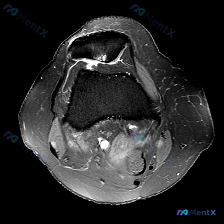

刚整理了一份很有代表性的踝关节影像读片病例,分享一下我的分析思路,这个陷阱很多年轻医生都容易踩。 病例基本影像信息 本次仅提供踝关节MRI T1序列轴位图像,核心读片结果如下: 1. 骨性结构:胫骨远端、腓骨远端骨质信号正常,骨皮质完整,未见骨折、骨质破坏,关节面轮廓清晰,无明显骨赘形成 2. 软组...